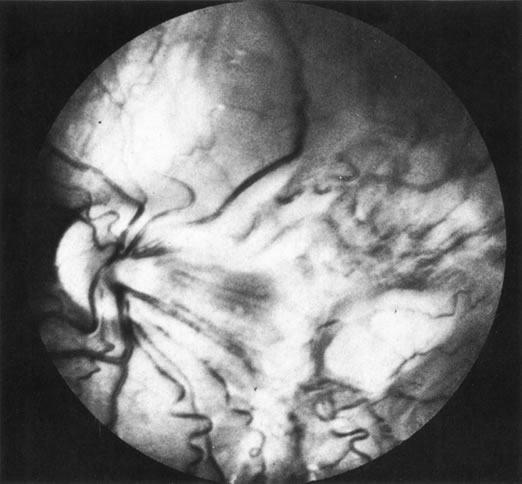

Necrotic melanomas account for approximately 5% of uveal melanomas; in the majority of cases, there is intraocular inflammation accompanying the cataract.7–9Figures 1 and 2 demonstrate a typical case. The patient had a long history of unilateral decreased vision. The eye had become painful 1 month before admission, and he was referred for evaluation of uveitis. Clinically, there was a dense, unilateral cataract with significant intraocular inflammation, which was manifested as a ciliary flush with 2+ cells and flare. Media opacity obscured all fundus detail. An immersion B-scan demonstrated a large intraocular tumor that was most consistent with a uveal melanoma. The eye was removed, and the diagnosis was confirmed histologically.10

Fig. 1. A unilateral media opacity in an adult, requiring that either a foreign body or an intraocular tumor be ruled out. The finding of a large episcleral (“sentinel”) vessel was consistent with either an intraocular tumor or an inflammation. An immersion B-scan helped determine the diagnosis (see Fig. 2).

Fig. 2. Immersion B-scan of the patient in Figure 1 demonstrates a uveal melanoma.